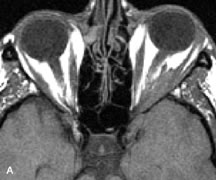

PATIENT PREPARATION Before MRI is performed, patients must be screened and prepared to avoid the potential hazards associated with the strong magnetic field. Patients who have ferrous aneurysm clips or cardiac pacemakers, who depend on life-support equipment, or who retain a possible metallic intraocular foreign body are not candidates for this imaging modality. MRI cannot be performed on obese patients who cannot fit into the bore of the magnet. Patients who are claustrophobic may not tolerate a prolonged period of study within the confines of the magnet, whereas others might do well if given a mild sedative. All worn metallic objects (e.g., necklaces, watches) should be taken off, credit cards set aside, and eye makeup removed before entering the room containing the magnet.5,20,34,35,36 NORMAL ORBITAL ANATOMY T1-weighted images provide the best anatomic details of the orbit because they display superior contrast resolution between normal structures (see Fig. 8). The vitreous has a long T1, resulting in an intermediate signal similar to brain, whereas the crystalline lens and sclera appear dark because of a longer T1 and short T2. The extraocular muscles, like all skeletal muscles, demonstrate a moderately long T1 and short T2 and highly contrast with the intense signal of the surrounding orbital fat (adipose tissue has an extremely short T1). The lacrimal glands appear as mottled areas of reduced intensity of the signal from the orbital fat in the lacrimal fossa. The optic nerves are seen with the same signal intensity as brain white matter and are hypointense relative to the orbital fat because their Tl is longer than the Tl of fat but shorter than the Tl of water. Cortical bone is not well delineated because it contains little free water, yielding minimal signal in MRI, and thus appears dark on all pulse sequences. This feature explains why MR images of the orbital apex and intracanalicular portion of the optic nerves are superior to comparable CT scans. Partial volume averaging of the bones in these regions obscures soft tissue details on CT images, whereas MRI reveals the signals only from the soft tissue structures with no cortical bone input. Bone marrow, on the other hand, is seen as a relatively intense signal because of its high fat content (see Fig. 8).37,38 T2-weighted pulse sequences are not ideal for imaging normal anatomy; however, they are particularly useful in revealing pathologic conditions (see Fig. 9). T2-weighted studies are most easily recognized by a bright vitreous signal. ORBITAL DISEASES Vascular Lesions Cavernous hemangiomas appear as well-circumscribed, smooth, usually intraconal masses that are isointense to muscle on T1-weighted images and hyperintense on T2-weighted images (Fig. 12). Patchy early enhancement is typically followed by diffuse, more homogeneous enhancement.39 The internal architecture of the mass, including septation and internal vasculature, may often be appreciated with high-quality orbital imaging.40 Lymphangiomas consist of ectatic vascular channels within a connective tissue stoma with varying degrees of lymphoid cellularity. On MRI, these tumors are typically poorly circumscribed, multicompartmental, and heterogeneous, often showing cystic dilations with fluid levels (Fig. 13). The signal characteristics within lymphangiomas vary considerably, reflecting cystic and solid components and the varying paramagnetic characteristics of blood at different stages of degradation.40–42 Acute hemorrhage appears hypointense on both T1- and T2-weighted formats. Methemoglobin present in subacute hemorrhage (3 to 14 days) leads to hyperintense signal on both T1- and T2-weighted images.41 A small percentage of lymphangiomas appear radiologically indistinct from orbital cavernous hemangiomas.43 Orbital varices are venous malformations that expand with increased systemic venous pressure, such as with Valsalva maneuvers. Because rapid acquisition of images during a Valsalva maneuver is important in imaging such a lesion, conventional or spiral CT is currently the modality of choice.44 MRI is an excellent modality for demonstrating enlargement of the cavernous sinus and dilation of the superior ophthalmic vein in patients with high-flow carotid-cavernous fistulas (Fig. 14).37MRA may be helpful in the evaluation of the venous outflow pattern. The rapidly flowing blood in these vascular structures carries the excited protons out of the section before they can be imaged, resulting in their dark appearance.5 In low-flow dural arteriovenous malformations, MRA may help define the arterial feeding vessels.45 Neural Lesions MRI is more effective than CT in delineating the intracranial optic nerves, chiasm, and optic tracts and, for this reason, is the preferred imaging modality in the evaluation of optic nerve disorders. The spatial relationships and image contrast of the orbital tissues with intraorbital optic nerve tumors is comparable between the two imaging modalities. The normal nerve is isointense to brain and appears enlarged and kinked owing to infiltration of an optic nerve glioma on T1-weighted images. Gliomas appear hyperintense on T2-weighted images and may be heterogeneous owing to cystic areas within the tumor. Contrast enhancement is variable.46 Intraorbital and intracranial optic nerve sheath meningiomas are usually isointense to cortical gray matter on Tl-weighted images and remain isointense on proton density studies (Fig. 15). Gd-DTPA is useful in delineating the intracranial extension of optic nerve meningiomas.7,47 The hyperostosis of bone and calcification associated with meningiomas are not demonstrated as well on MRI studies as on CT scans.20,37 Gd-DTPA–enhanced MRI also appears promising in the study of the permeability of the blood–brain barrier in selected optic neuropathies.22,48 MRI may reveal an enlarged optic nerve and some degree of contrast enhancement in cases of optic neuritis.49 Muscle Disorders Extraocular muscle enlargement in patients with thyroid-associated orbitopathy is demonstrated equally well with CT and MRI studies. However, the superior tissue contrast on MR images reveals better details of the relationships of the optic nerve to the thickened muscles at the orbital apex (Fig. 16).50 In addition, MRI may be able to differentiate between muscles that are enlarged as a result of edema and active inflammation and those enlarged because of fibrosis by their T2 relaxation times.21 Quantitative MRI was not found to be accurate in predicting the success of low-dose orbital irradiation.51 However, a muscular index relating the diameters of the rectus muscles to the bony orbital dimensions was useful in predicting optic nerve compression.52 MRI is also effective in imaging orbital tumors of mesenchymal origin, such as rhabdomyosarcoma, particularly in the assessment of extension into the anterior and middle cranial fossae (Fig. 17).37 The lack of any pathognomonic radiologic features necessitates rapid orbital biopsy when rhabdomyosarcoma is suspected. Osseous Lesions In general, CT is the imaging modality of choice when details of quantity and quality of bone are needed; however, abnormalities of bones can be detected indirectly by MRI. Cortical bone appears black (signal void) on MR images because of its low proton density and free-water content. The absence or discontinuity of the signal void of the orbital walls may represent bony destruction or fracture. Hyperostosis associated with prostate metastases or meningioma is visualized as areas of black smudging.50,53 Diseases in which the bone is replaced by pathologic tissues with a high free-water content, such as fibrous dysplasia, are well demonstrated on MRI. An intermediate signal intensity on T1-weighted images and hypointense signal on T2-weighted images is representative of fibrous dysplasia. Enhancement on post–Gd-DTPA MR scans is seen and is more evident in areas that are less mineralized.54 Cystic Lesions Dermoid cysts appear as rounded, well-defined lesions typically contiguous with an orbital bony suture. The high-intensity signal on T1-weighted images is attributed to the sebaceous-produced lipid contents (Fig. 18).31,50 Mucoceles may demonstrate a hypointense or hyperintense signal on MR images, depending on the concentration of proteinaceous or inflammatory fluid components. The integrity of the bony walls of the expanded sinus cavities cannot be assessed on MR as well as by CT.37,50,55,56 A high-signal intensity on Tl- and T2-weighted images is characteristic of orbital chronic hematic cysts because of the blood-breakdown products within the cysts.57 Trauma Although soft tissue relationships are usually better demonstrated on MRI, the evaluation of craniofacial bony trauma is preferable with CT. For example, prolapse of orbital fat through a fracture site and hemorrhage of adjacent tissues are demonstrated in an MR image, but the actual fractured bone is not imaged. Three-dimensional MRI of the orbit in subacute trauma has been described,58 although its precise role is not currently established. MRI has been suggested to be superior to CT in detecting intraorbital wooden foreign bodies.59,60 In a series of penetrating orbital injuries with organic foreign bodies, however, MRI was able to identify the foreign body in only four of seven cases.61 With an in vitro model for wood foreign body, McGuckin and colleagues concluded that CT was the imaging modality of choice.62 A careful history and, in selected cases, plain films to rule out a metallic foreign body are crucial before MRI is considered in patients with periocular trauma. MRI is particularly helpful in the detection and characterization of subperiosteal hematomas of the orbit (Fig. 19). They are most commonly seen in the subperiosteal space of the superior orbit as well-defined masses following a traumatic injury. The signal intensity varies depending on the acute, subacute, or chronic nature of the hematoma, based on the stage of blood degradation. Fresh hemorrhages are hypointense on T1-weighted images and hyperintense on T2 images. Hematomas that are 1 to 7 days old are hypointense on both T1- and T2-weighted images. T1-weighted images of hematomas more than a week old are hyperintense due to the oxidation of deoxyhemoglobin to methemoglobin, whereas the T2 images remain hypointense.63 Metastatic Tumors Breast carcinoma metastatic to the orbit has been demonstrated to be hypointense to the surrounding orbital fat on T1-weighted studies and hyperintense on T2-weighted images and has an affinity to the extraocular muscles (Fig. 20).50,64 The MRI characteristics of prostate carcinoma metastatic to the orbit have been described as involving the greater and lesser wing of the sphenoid, orbital roof, and optic canal. Diffuse bone hypertrophy with isointense or slightly hyperintense tissue on T1-weighted images represents the osteoblastic carcinomatous bone infiltration. Contrast enhancement is variable on T1-weighted and fat-suppressed images.65 Most other metastatic tumors also have a lower intensity signal on T1-weighted images and appear to displace or infiltrate normal orbital structures; however, their signal characteristics are variable on T2-weighted MR images.66 Many metastatic tumors demonstrate bright contrast enhancement with Gd-DTPA. Infectious Disorders MRI findings of preseptal and orbital cellulitis typically include increased signal intensities on T2-weighted images of the eyelids and orbital fat, respectively, due to the increased water content of the tissues. Since most cases of bacterial orbital cellulitis are associated with paranasal sinusitis, hyperintense signals of the affected sinuses may also be found on T2-weighted images as well as enhancement of polyps and granulation tissue on postgadolinium T1-weighted MR images. Subperiosteal abscess formation may occur due to contiguous spread of infection from the paranasal sinuses and appear on MRI as an area of intermediate signal on T1-weighted and proton-weighted MR images. The abscess may appear slightly hyperintense compared with muscle on T2-weighted scans with the necrotic contents having the greatest intensity.67 MRI and MRV are more sensitive than CT in revealing cavernous sinus thrombosis. Engorgement of the cavernous sinus, extraocular muscles, and ophthalmic veins is seen with hyperintensity of the thrombosed sinuses evident on all pulse sequences. The enlarged, thrombosed superior ophthalmic vein appears less hypointense than the normal contralateral ophthalmic vein, and hyperintensity within the lumen of the vessel may be seen on T1- and T2-weighted MR images.68 Inflammatory and Lymphoproliferative Lesions Inflammatory conditions of the orbit, both idiopathic (inflammatory pseudotumor) and those of known causes, have been found to be hypointense to fat and isointense to muscle on Tl-weighted studies and isointense or slightly hyperintense to fat on T2-weighted images (Fig. 21).50,64,69 The more fibrous or sclerosing varieties have less signal intensity on T2-weighted images. Marked enhancement is seen in pseudotumor infiltrates after gadolinium administration.70 The same signal characteristics are demonstrated in patients with Tolosa-Hunt syndrome, with mass lesions seen in the cavernous sinuses and orbital apices.71 Lymphomas have MRI characteristics similar to those of inflammatory lesions in that they are hypointense to fat and isointense to muscle on T1-weighted images (Fig. 22). They may appear hyperintense to fat on T2-weighted images, perhaps owing to less fibrosis than that seen in orbital inflammatory pseudotumor, although this is not a consistent finding.31,50,66 Lymphoid tumors typically enhance moderately after contrast injection. Unfortunately, studies have shown that tumor density and homogeneity are similar between inflammatory and malignant orbital infiltrates, and MRI cannot differentiate these lesions.72,73 Lacrimal Gland Tumors Lacrimal gland lesions present special problems in diagnosis and management. Pleomorphic adenoma (benign mixed tumor) should not be biopsied, but rather excised in toto. On the other hand, for lymphoma and inflammatory infiltrates, incisional biopsy is more appropriate than complete excision of the lacrimal gland. Thus, preoperative clinical and radiologic evaluation are especially crucial in planning appropriate surgical management. Pleomorphic adenomas demonstrate long T1 and T2 signal characteristics. They may show heterogeneity on T2-weighted images74 and moderate to marked enhancement with contrast.75 Signal characteristics of adenoid cystic carcinoma include hypointensity to fat on T1-weighted images, hyperintensity to fat with increased T2 weighting, and isointensity to fat on proton density-weighted studies (Fig. 23).31,75 Secondary bony alterations of the lacrimal fossa associated with lacrimal gland tumors, such as remodeling (benign mixed tumor) or destruction (adenoid cystic carcinoma), are seen indirectly on MR images; however, bone windows on CT scans provide better delineation of these changes. In contrast to the round or globular appearance of benign or malignant epithelial tumors of the lacrimal gland, lymphoproliferative tumors usually appear to be molding or draping onto the globe and the surrounding bony orbit. LACRIMAL DRAINAGE SYSTEM DISORDERS MRI with surface coils provides excellent spatial resolution and tissue-specific signal intensities of the lacrimal drainage system. These parameters have been found useful to more accurately demonstrate the extent of lesions in the lacrimal sac and differentiate long-standing mucoceles from solid tumors than CT.76 Physiologic studies in patients with tearing disorders now include MR dacryocystography, in which Gd-DTPA is either placed topically in the conjunctival fornix or injected by cannulation into the lacrimal sac. They provide a detailed morphologic and functional analysis of the lacrimal excretory system; however, they are no more sensitive than digital-subtraction dacryocystography or CT dacryocystography.77–79 INTRAOCULAR TUMORS On MRI, uveal melanomas have a typical appearance that helps to differentiate them from other primary and secondary intraocular tumors as well as choroidal detachments. Pigmented melanomas are hyperintense on Tl-weighted images, hypointense on T2-weighted studies, and hyperintense on proton density–weighted examinations (Fig. 24).30,31,50,80–82 These signal characteristics have been attributed to the paramagnetic properties of melanin because of stable free radicals that shorten the T1 and T2 relaxation times. Moderate enhancement is seen on postgadolinium T2-weighted images. Gadolinium-enhanced T1-weighted images are particularly sensitive in detecting choroidal melanomas.83 MRI may be less sensitive in detecting extrascleral extension of tumor than echography performed by an experienced ultrasonographer.84 Tumors metastatic to the choroid are hyperintense on T1- and T2-weighted images.24 The signal characteristics, however, may be similar to those seen with choroidal melanoma. Choroidal hemangiomas, on the other hand, have an intermediate signal on T1-weighted sequences and become hyperintense on T2-weighted images50 as well as proton density–weighted images.81 Retinoblastomas display moderate signal intensity on T1-weighted studies and a low signal on T2-weighted images.31,80,85 Calcification can be easily detected by CT and ocular ultrasonography but is not imaged by MRI.25,50 The presence of optic nerve involvement is best evaluated by MRI. ACQUIRED ANOPHTHALMIA When an eye is removed owing to tumor or trauma, an implant is typically placed in the intraconal space. MRI may be useful in defining the size, shape, and position of such orbital implants.86 Porous hydroxyapatite or polyethylene implants are preferred by many surgeons performing enucleation or evisceration. A porous implant offers the possibility of supporting a motility coupling peg to increase the movement of the overlying prosthesis. MRI with contrast is used by some surgeons to evaluate the degree of fibrovascular ingrowth in hydroxyapatite87 and porous polyethylene88 implants prior to motility peg placement. |